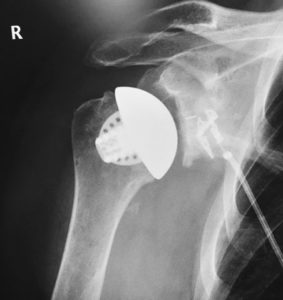

Das Equinoxe® Schaftlose Schultersystem ist eine knochenerhaltende Prothese für die anatomische totale Schulterarthroplastik. Die im 3D-Druckverfahren aus Titan hergestellte poröse Struktur ist für eine optimale biologische Fixierung ausgelegt. Das schaftlose Cage fördert durch die poröse Oberfläche sowie die Formgestaltung ein An- bzw. Durchwachsen des Knochens.